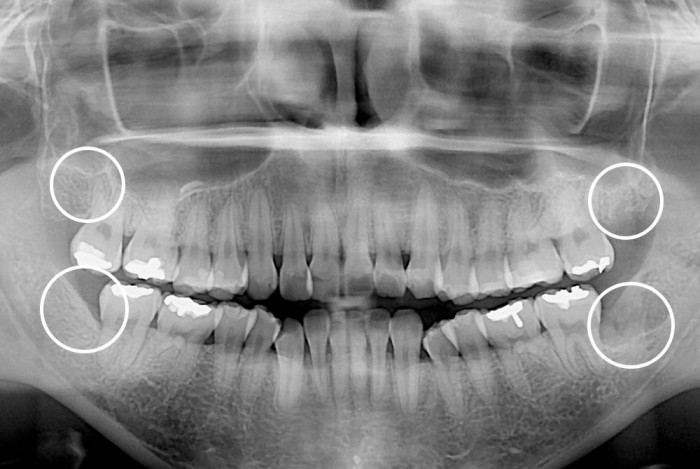

[사랑니] 사랑니

치료후 : 2020-03-23

세종치과는 구강악안면외과학 박사이신 원장님이 발치하는 치과입니다.